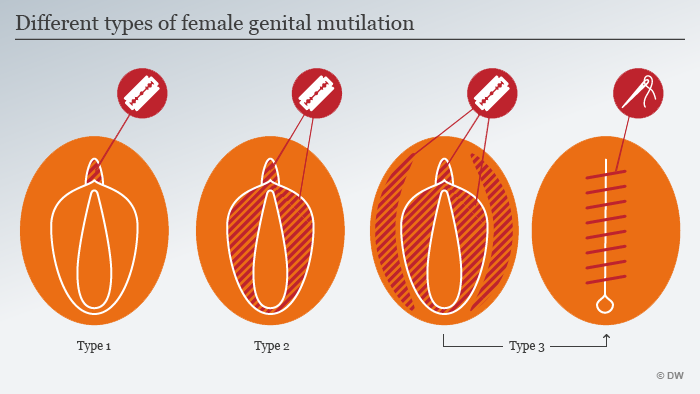

क्या है महिलाओं का खतना यानि FGM:

महिलाओं का खतना यानि FGM (Female genital mutilation) एक ऐसी प्रक्रिया है जिसमें महिलाओं और लड़कियों के योनी के भगोष्ठ को गैर-चिकित्सा कारणों से काटकर निकाल दिया जाता है| इस प्रक्रिया का कोई शारीरिक फायदा महिलाओं को नहीं होता है| इस प्रक्रिया में अत्यधिक रक्तस्राव होता है और इसके बाद महिलाओं में पेशाब की समस्या उत्पन्न हो जाती है. साथ ही कई तरह के संक्रमण और प्रसव के दौरान जटिलताएं भी उभर आती हैं, जिसके कारण कई बार नवजात की मौत भी हो जाती है. जब लड़की छोटी होती है तभी उसके साथ इस तरह की क्रिया को अंजाम दिया जाता है|

महिलाओं का खतना यानि FGM (Female genital mutilation) मे चार से पांच साल की बच्चियों की योनी की भगनासा (Clitoris )और उसके आसपास के भगोष्ठ को छील दिया जाता है| कई बार इस से बच्चियों की मौत भी हो जाती है|

क्या है खतना (FGM) की प्रक्रिया (खतना प्रोसेस इन फीमेल):